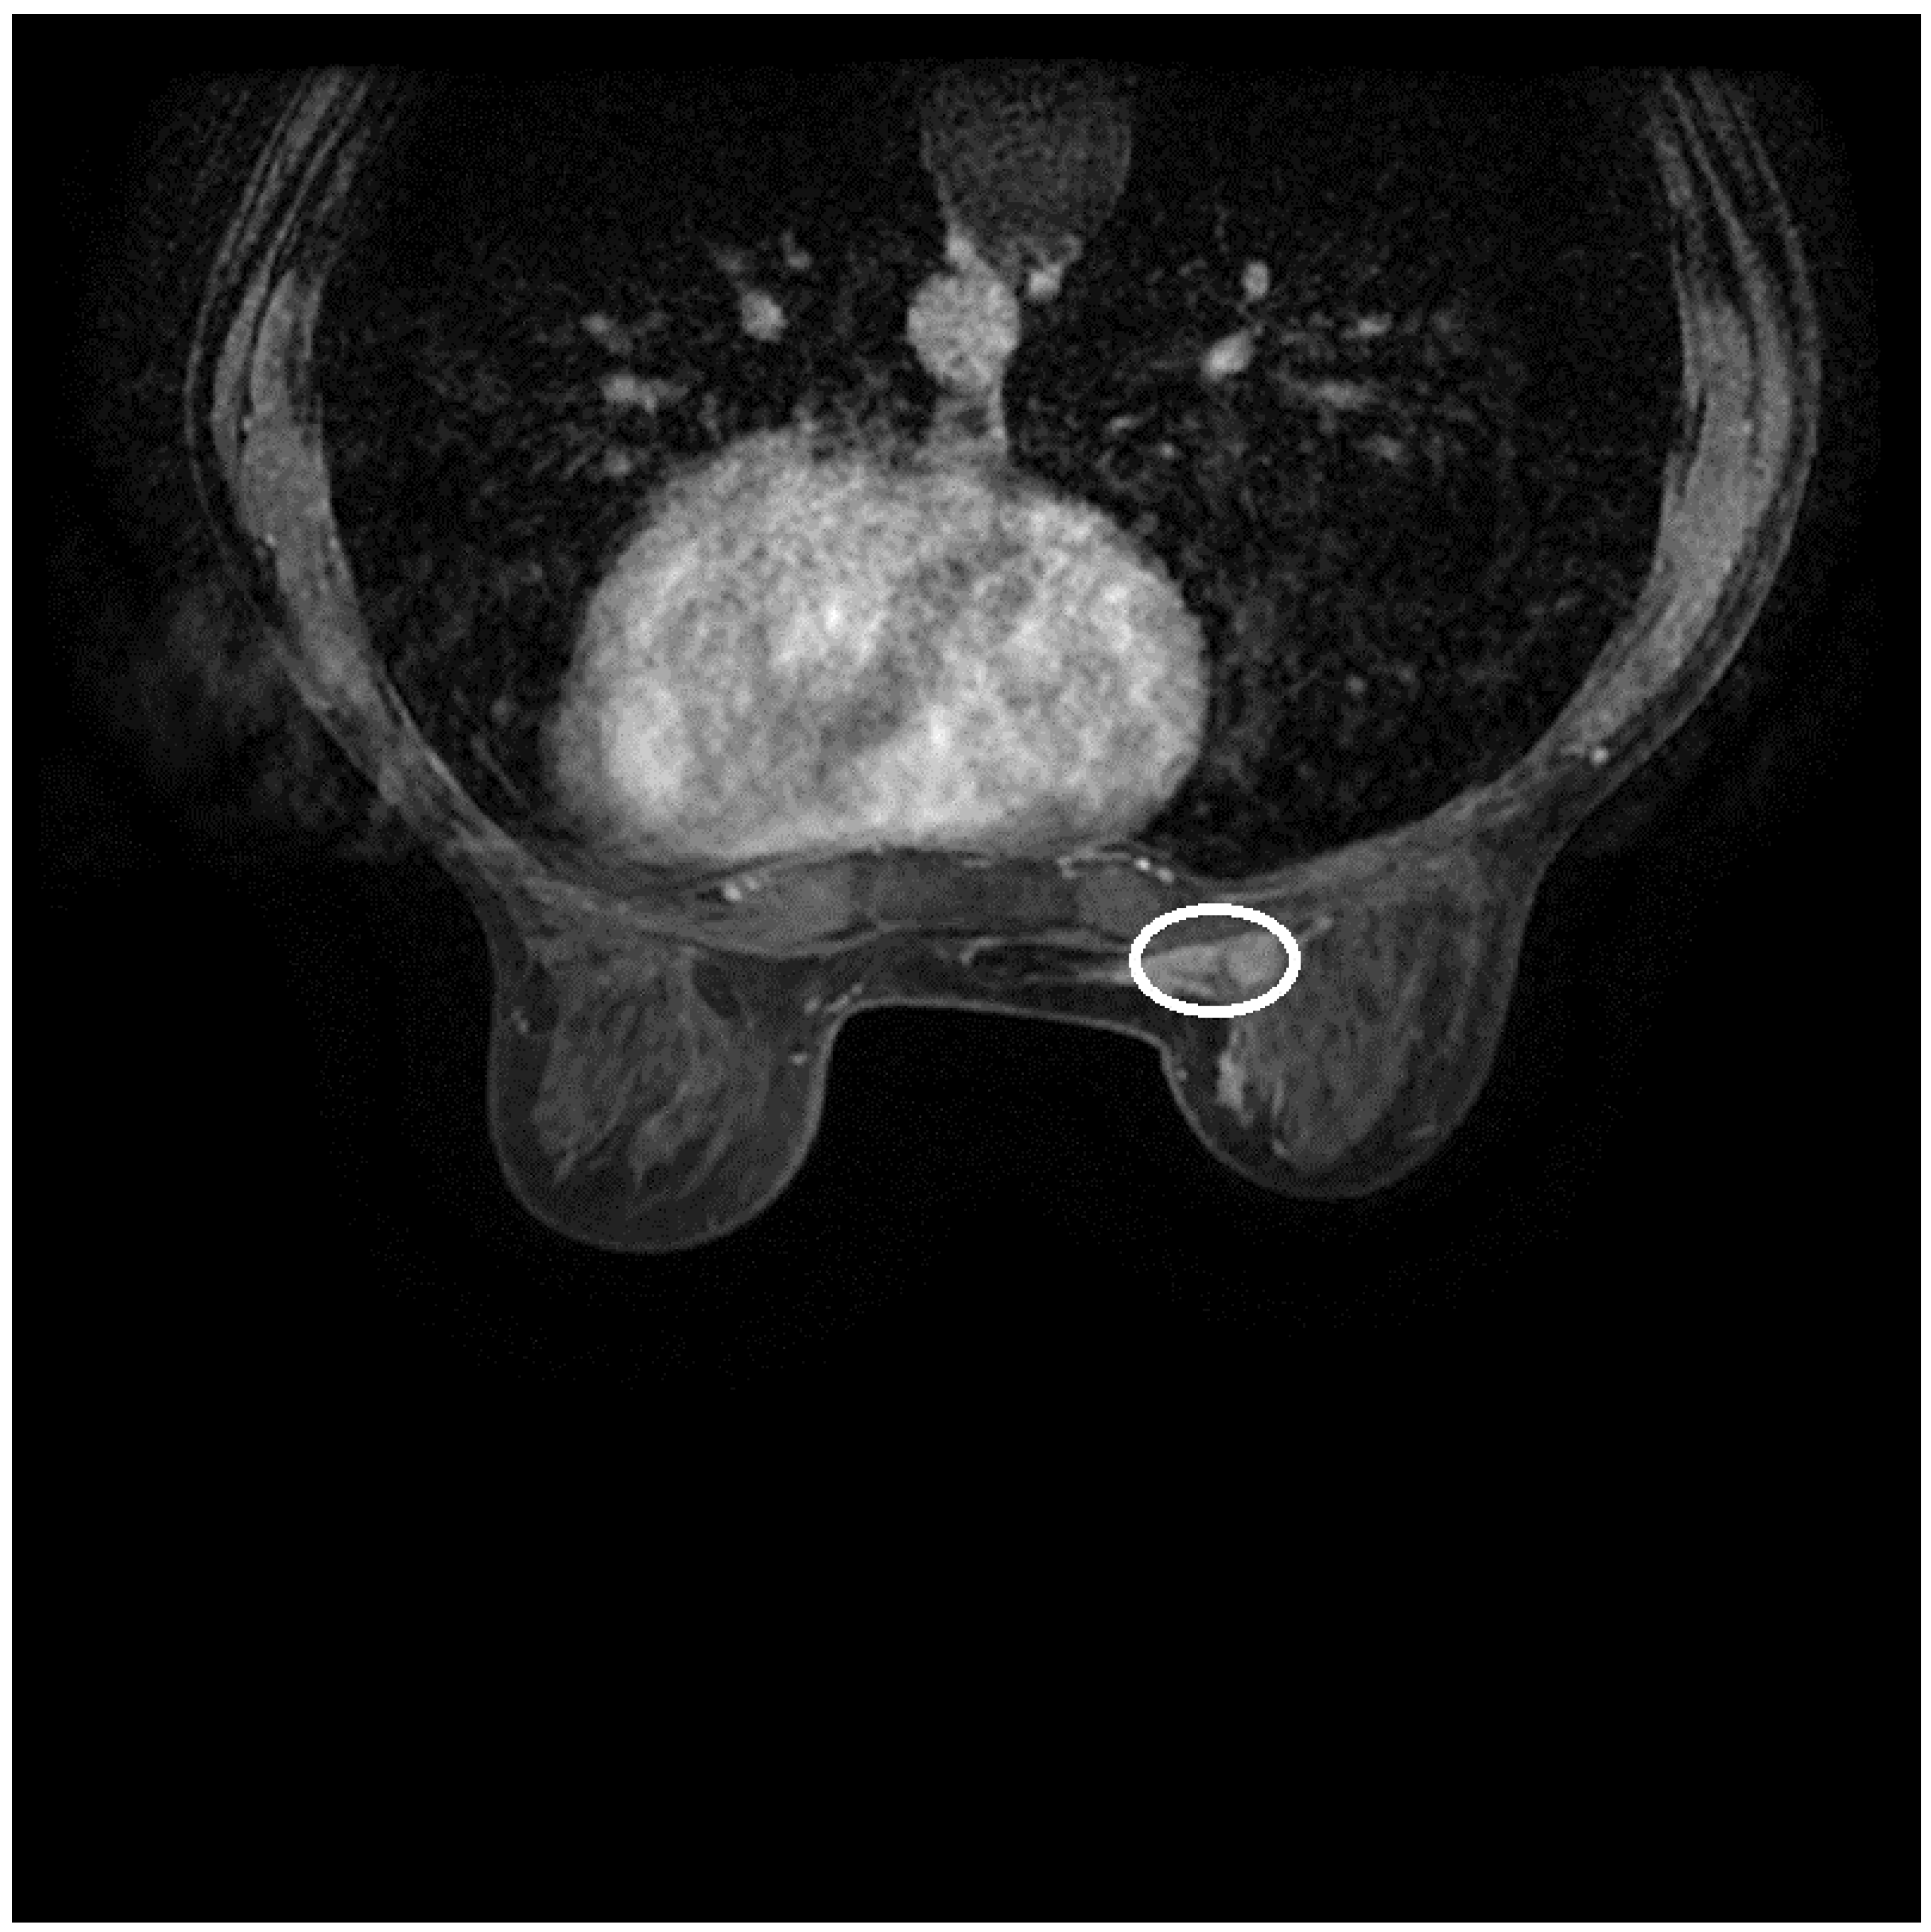

2.2. Imaging

- The diagnosis of invasive ductal carcinoma and its classification as cT3N1M0 and pT3N1M0 for the primary right IMR accessory breast cancer, stage IIIA, and cT2N0M0 of the native right breast cancer;